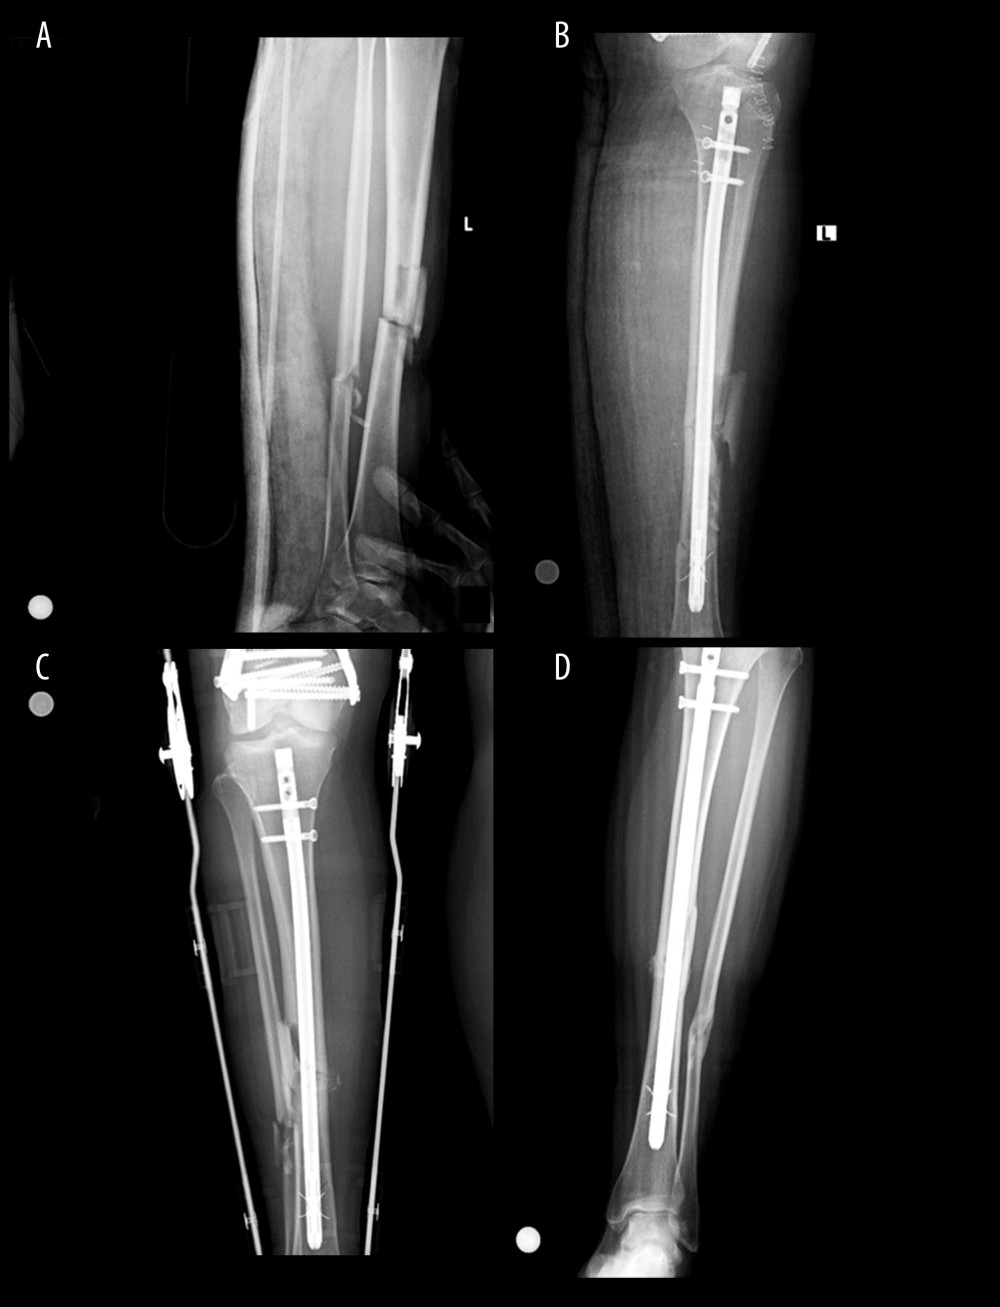

From www.researchgate.net

43yearold male femur fracture A) fracture radiography B Old Bone Fracture Radiology Some of these missed diagnoses are followed by excellent functional recovery, and later only radiographic deformities can be found as. The images are of a patient with a typical bamboo spine as a result of ankylosing spondylitis. Within 48 hours, chemotactic signaling mechanisms attract the inflammatory. Patients who sustain an acute vertebral fracture after a traumatic event experience damage to. Old Bone Fracture Radiology.